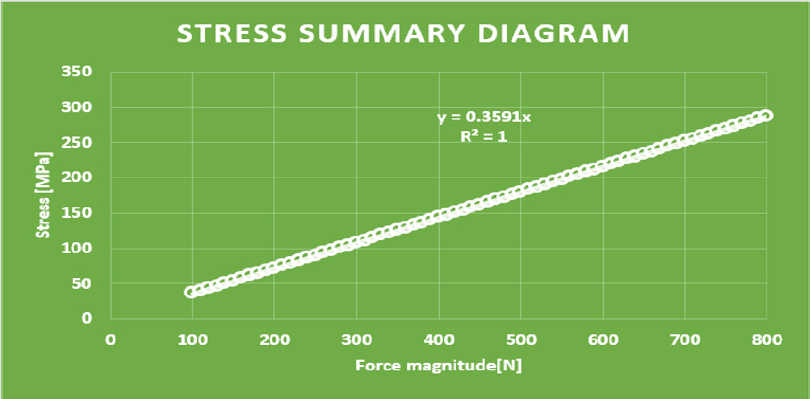

Distant forces were used as they would normally act on the implant from the dental crown. We used data obtained from scientific literature according to which magnitude occlusal forces can be between 100 and 800 N. In the first analysis, maximum 800 N occlusal force was defined. Its result is presented in Figure 7 It is notable that stresses only raised at the acting point of the force. Stress intensity was 287.28 MPa for maximum occlusal load. Another scenario was also investigated in which the frontal part of the implant was loaded with the lowest, while the back of the implant was loaded with the highest occlusal forces. Figure 8 presents the results of this loading scenario with the maximum stress level of 207.6 MPa. It is notable in this case that highest stresses raised at the back of the implant at the acting points of the forces. Different force variations were all analysed from minimum to maximum loads. Figure 9 shows the set of completely linear results. Highest stress intensity was 287.28 MPa for maximum occlusal forces. The studied implant was inserted after manufacturing. Implant fitting to the bone ridge of the patient can be seen in Figure 10.

In our mechanical analyses, the highest stress intensity was 278.28 MPa for maximum occlusal load. Yield strength of Grade 23 Ti-6Al-4V alloy is 760MPa, which means if we calculate maximum permissible stress with the safety factor of 2, the structure will still be safe. Volume reduction was successful. Consequently, the mass of implanted titanium alloy was reduced in the patient. Further studies will be conducted to further decrease the amount of titanium material.